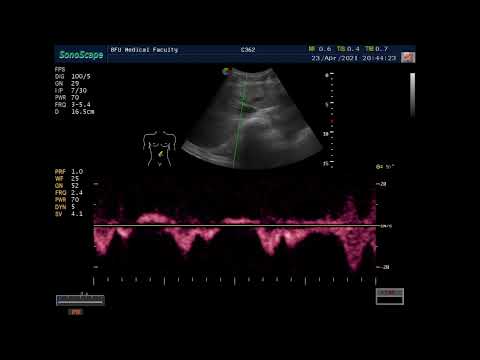

Лекция для врачей цикла первичной переподготовки по ультразвуковой диагностике в БФУ им. И. Канта (г.Калининград). Уважаемые врачи! Циклы первичной переподготовки по ультразвуковой диагностике (504 часа) под руководством профессора В.Изранова в БФУ им. И. Канта (г.Калининград) проходят ежегодно в сентябре – декабре и феврале - июне. Формы обучения очная и дистанционная. Контакты отделения ДПО БФУ им. И. Канта для записи на курсы: polinaligatyuk@mail.ru vmyshlennik@kantiana.ru +7 911 866-66-77 Наши циклы НМО в 2021 г.: Ультразвуковая диагностика диффузной патологии печени Ультразвуковая диагностика заболеваний поджелудочной железы Ультразвуковая диагностика заболеваний желчного пузыря и желчевыводящих путей Ультразвуковая диагностика заболеваний молочных желез Ультразвуковое исследование печени. Проблемы нормы С сентября 2021 г. открыты дополнительные циклы НМО: Основы эхокардиографии УЗИ в гинекологии УЗИ щитовидной железы